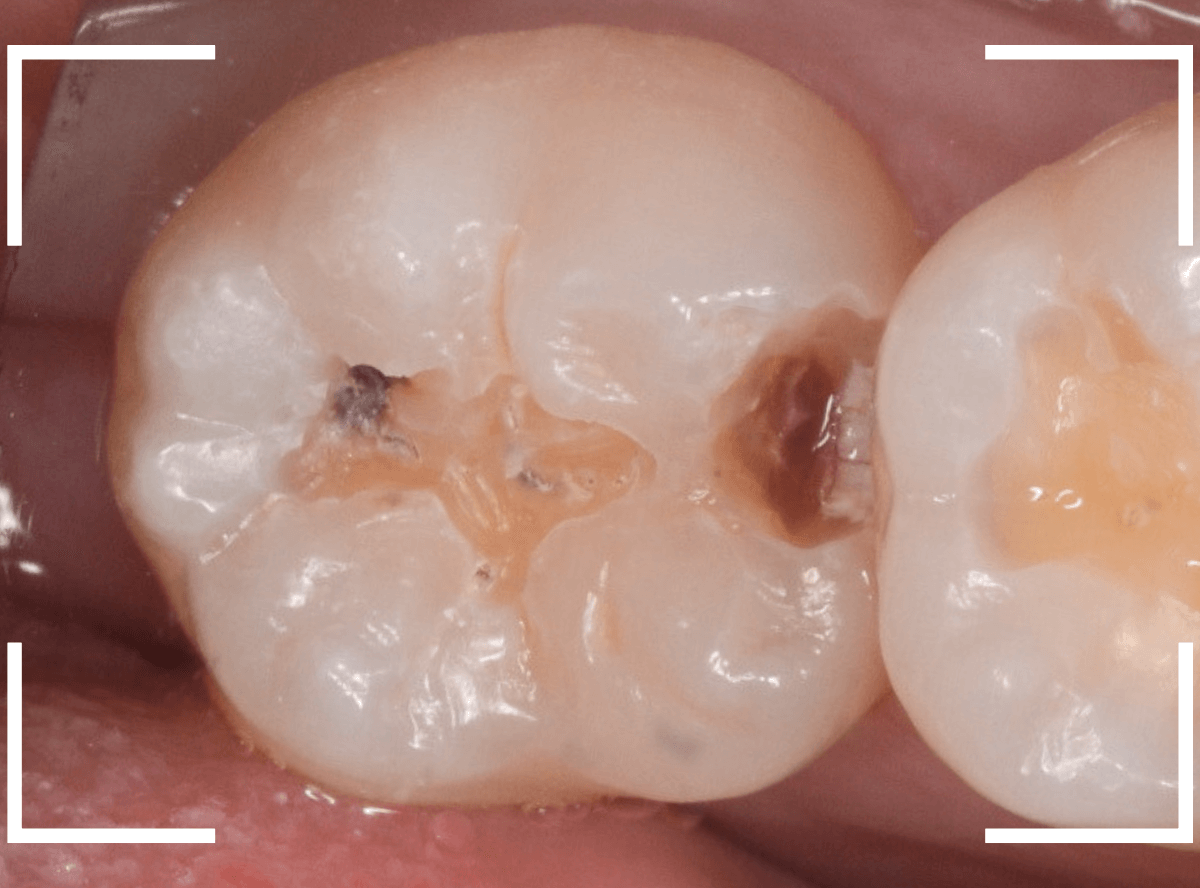

〇部が虫歯の部分です。

写真で見てわかるように、常に舌が歯に触っているような状況です。

このような場合、虫歯を見つけづらいですし、治療の難易度もあがります。

虫歯の治療を開始します。

隣の歯とのすき間を中心に広い虫歯になっていました。